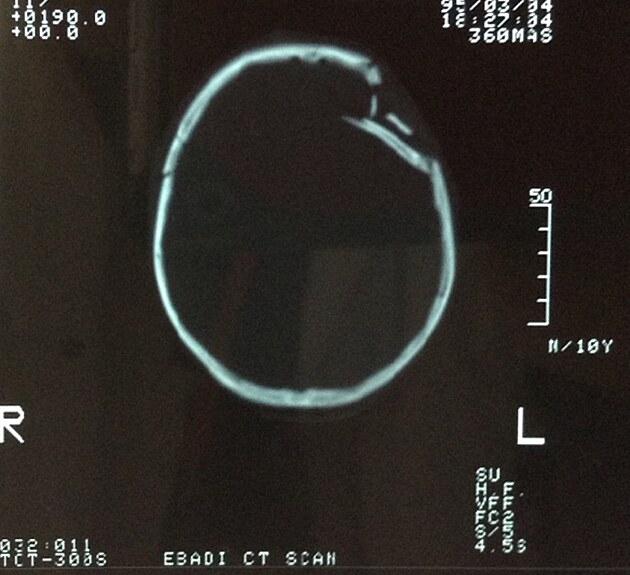

Holím mu hlavu a znovu a znovu mě štve, proč tyhle děti? Zvenku to nevypadá dramaticky, taková malá kožní ranka vlevo na čele směrem k temeni. Když to ale zlehka prohmatávám, je tam místo kosti houba, která přesně odpovídá tomu, co jsem viděl na CT. Je to blíž střední čáře, než jsem čekal. Tam se bojím žilního splavu. Otevřít ho a máme tu operaci v cukuletu hotovou … Místo standardního řezu od temene dolů po hlavě přes místo imprese, jak nás to učili neurochirurgové v Kolíně nad Rýnem, volím sofistikovanější lalok, protože se sem a na tento typ zlomeniny prostě hodí.

Když lalok s galeou odklopím, mezi úlomky kostí leží měkké obláčky mozkový tkáně. Víc, než jsem kdy u jiných svých pacientů viděl. Opatrně vyjímám úlomek, který je do mozku nejvíce zabořený, a pak hledám strategii, jak vypáčit ven ten vpáčený zbytek, abych neudělal větší paseku, než která se odehrála během nehody. Dělat trepanační návrty se mi s manuální vrtačkou dneska moc nechce.

Nakonec úspěšně vypáčím všechny úlomky, naložím do fyziologickýho roztoku pro pozdější použití, a jímám se zkoumat díru do mozkové tkáně, která ústí asi 5 centimetry roztrženou tvrdou mozkovou plenou. Dost to difuzně krvácí, poslední hemoglobin toho kluka byl děsně nízký a krev nemáme aktuálně žádnou. Ale jsem trpělivej, někdy je lepší sušit a počkat.

Vyplachuju mozek žanetou, takovou velkou stříkačkou. To dělám od dob mý první kraniotomie na Haiti. Vypadá to brutálně, ale přesto je to hodně šetrný k mozkové tkáni. Víc se v tom nehrabu, pořád mi ještě zůstala posvátná bázeň před orgánem, kde sídlí člověk. Přemýšlím, jestli tam ty volné kostěné úlomky vrátím. Bojím se jistě příchozího otoku mozku a nerad bych mu bránil v místě, kde to bude vadit míň než tam, kde jsou na prodloužený míše centra pro dýchání.

Nakonec se rozhodnu čtyři největší kousky kosti opracovat téměř do kulata a vložim je na plenu volně jako knoflíky. Normálně je ještě provrtám a přišiju k okrajům zdravé lebeční kosti. Přes ně už jen hermeticky sešiju kůži. Celý to končím do hodiny. Jsem rychlejší, přesnější, mám to víc promyšlené i technicky vymakané. Ale ne proto, že bych byl šikovnej anebo talent. Bill Gates je jedním z nejlepších proto, že naprogramoval víc jak 10.000 hodin. Praktikovat. To nás dělá lepšími. Loučím se, jedu na základnu, do jedný v noci vybaluju, sprchuju prachem totálně slepený vlasy, snídám, obědvám, večeřím a piju za posledních 24 hodin najednou. A spim.